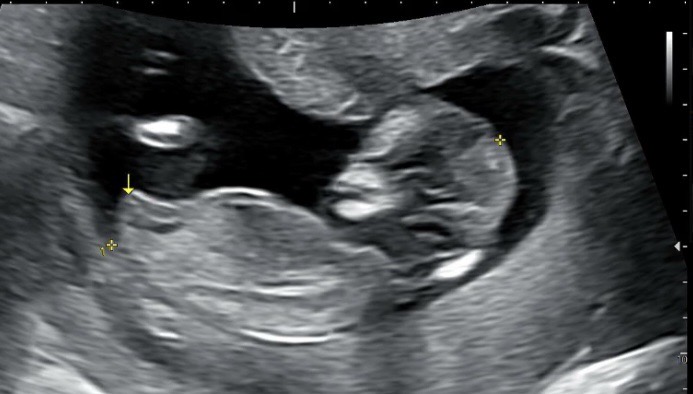

각도 고수님들 도와주세요 🥹🥹🥹 12주1일

혹시 각도 고수님들께서 보시기엔 어떠신가요? 감사합니다 👶🏻🥰🥹 12주 1일이에요!